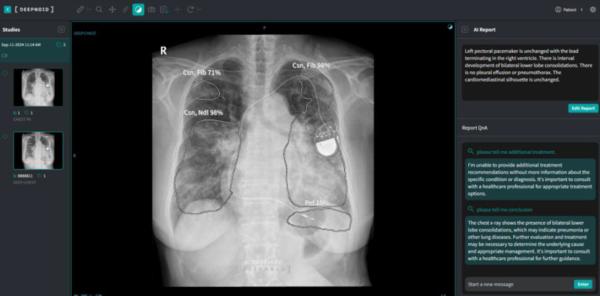

현재 딥노이드는 생성형 AI 기반 흉부 엑스레이 판독문 작성 솔루션 ‘M4CXR’을 개발하고 상용화를 준비 중이다.

M4CXR는 흉부 엑스레이에서 병변을 자동 검출하고, 80개 이상 질환에 대해 판독문 초안을 자동 생성하는 의료기기다.

딥노이드가 기존에 개발한 흉부 엑스레이 판독 보조 솔루션 ‘딥체스트’(DEEP:CHEST)보다 발전된 모델로 대형언어모델(LLM) 기술을 토대로 수많은 흉부 엑스레이 이미지와 판독문을 학습시켜 개발됐다.